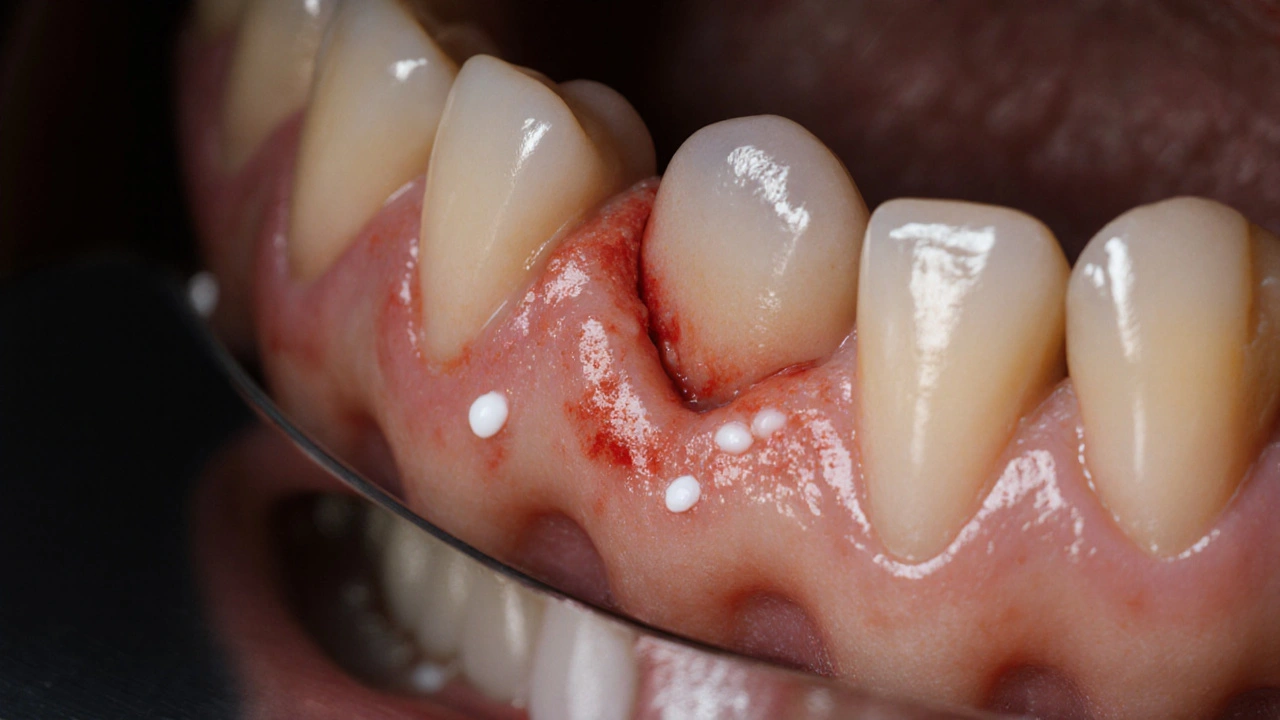

• oteklé, červené nebo krvácející dásně kolem zubu moudrosti

• malé bílé nebo žluté skvrnky na dásni nad zubem

Zubař nejprve zkontroluje stav zubu a dásní. Použije zrcátko a sondu, aby viděl, jak je zub zakrytý. Pokud je zánět akutní, nebudou vás hned operovat. Nejprve provede: